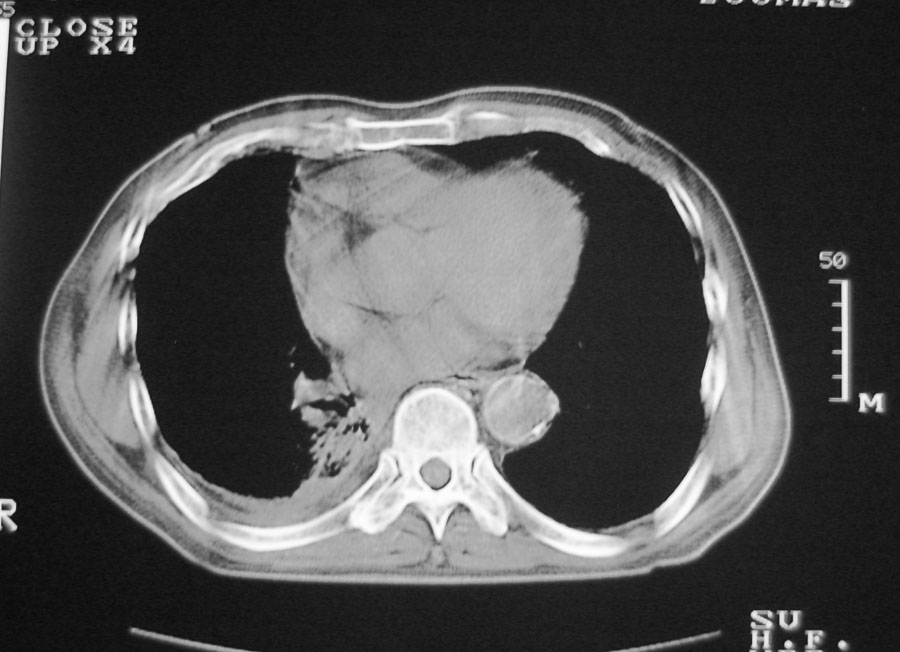

以下是引用hhcckk在2007-1-24 18:11:00的发言:[br]病灶周围胸膜反应比较明显,考虑炎症可能性大点,病人年龄较大,病灶成块状,肿瘤也不能排除,可可西里老师看片子的确很仔细,隔离肺暂时我觉得证据的说服力不大,上下层面显示条状影范围较长,可能是增厚的胸膜,可以做个增强鉴别一下

以下是引用天南地北在2007-1-24 18:00:00的发言:[br]1:右下肺内基底段类椭圆性肿快影:考虑1:右下球形肺炎2:右下肺隔离症,建议抗炎治疗后复查。[br]2:右肺及左下肺感染,右侧少量胸腔积液。